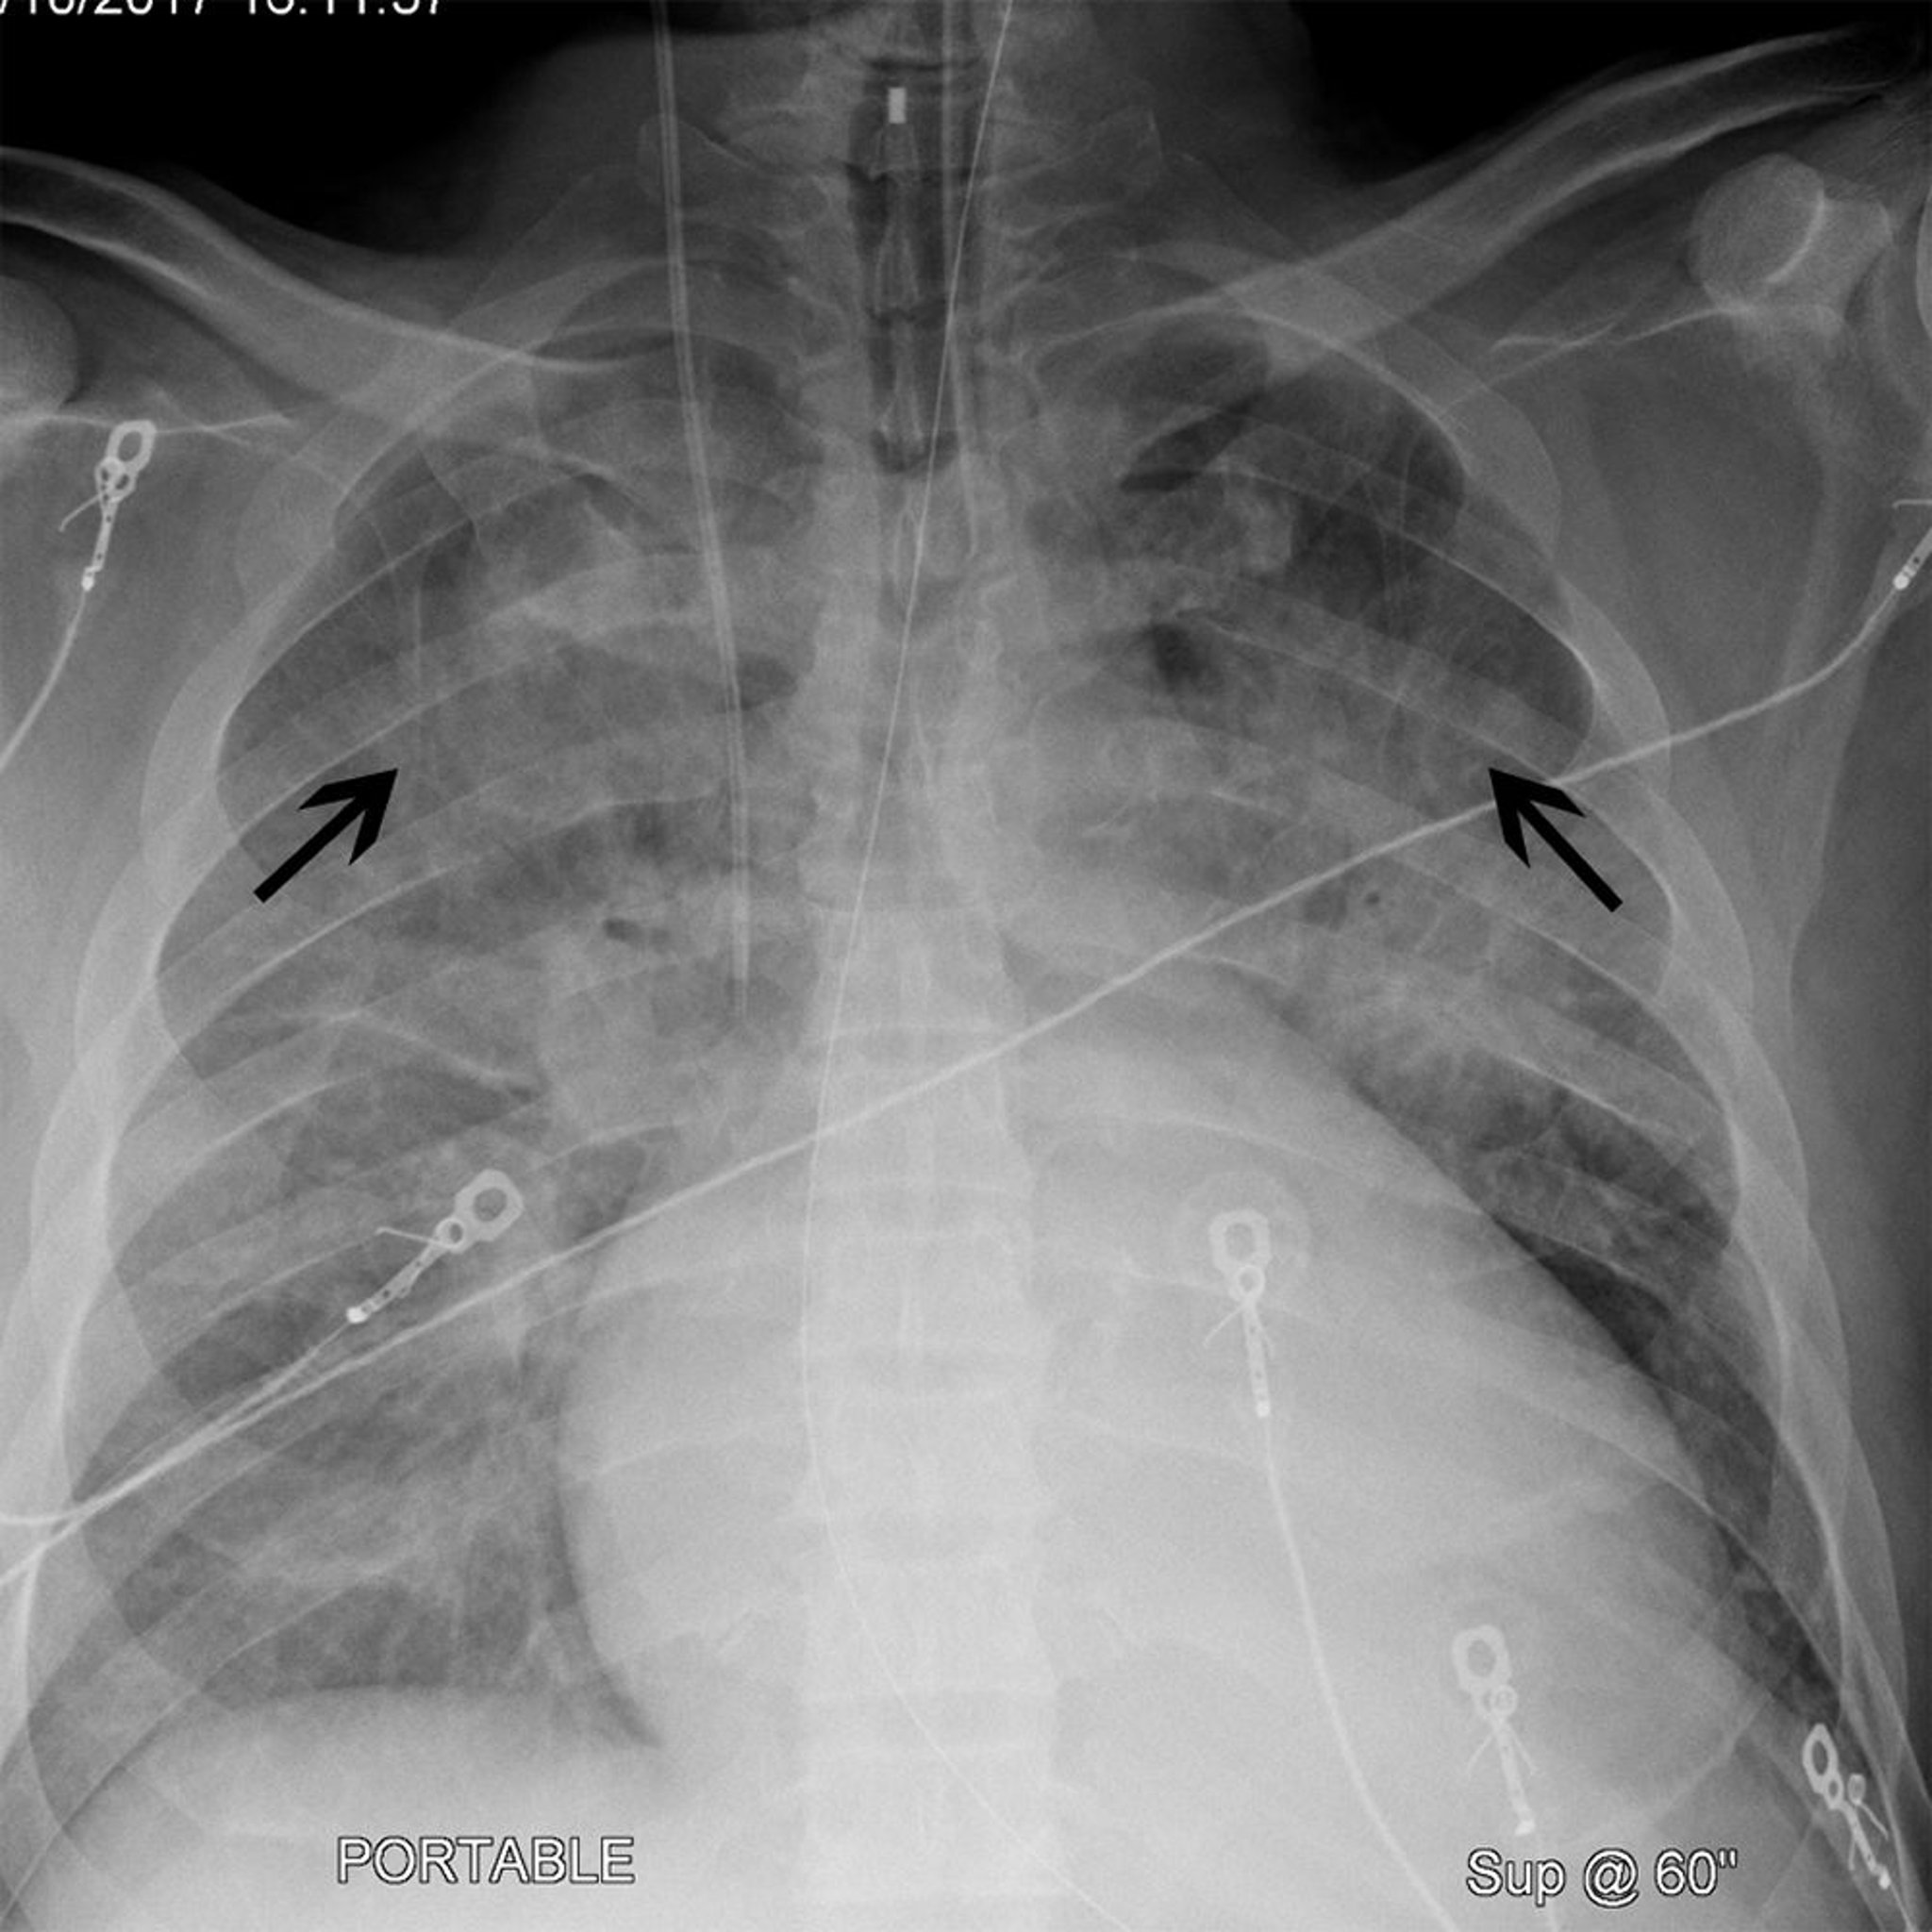

Röntgenthorax eines Patienten mit Kardiomegalie und Kephalisation

Dieser Patient hat eine Kardiomegalie (die Breite der Herzsilhouette beträgt > 50% des Thorax auf einer posterior-anterioren Röntgenaufnahme). Der Patient hat auch eine Kephalisation (schwarze Pfeile), wodurch die Lungengefäße des Oberlappens prominenter hervortreten. Diese Befunde werden häufig bei Patienten mit Herzinsuffizienz beobachtet.